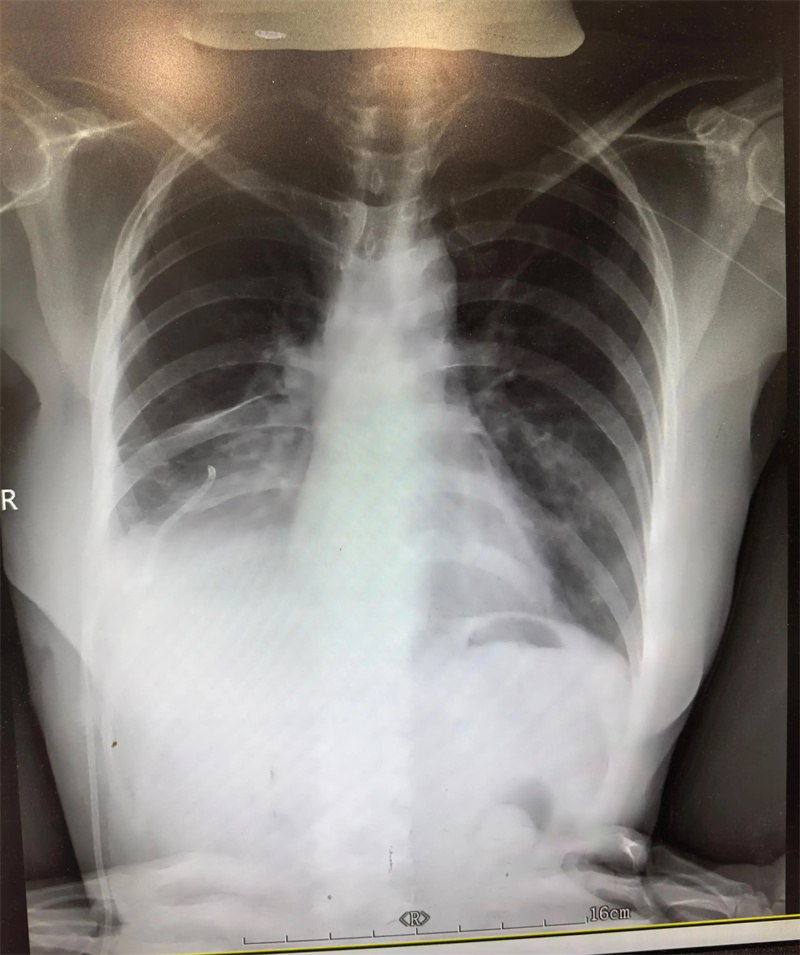

胸外科(二疗区)主任田子刚受邀参与,结合艾利影像学检查、肺功能评估及全身基础状况,与孙集思主任团队反复研讨手术指征、手术方式及围手术期风险防控要点。经过充分论证,最终确定实施“右肺下叶切除手术”。

手术当日,田子刚主任主刀,与团队成员密切配合,凭借精湛的技术,精准操作、精细剥离,完整切除病变肺组织,同时最大限度保留健康肺功能,手术过程十分顺利。